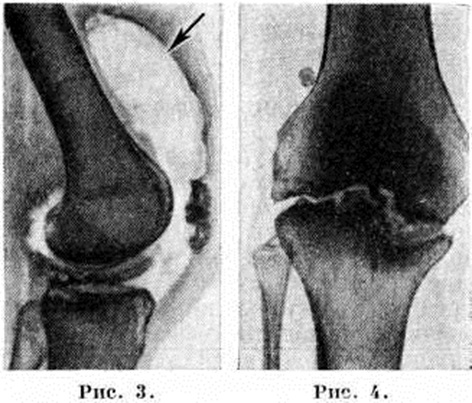

Большое значение для диагностики и дифференциальной диагностики различных форм Гонит имеет рентгенологическое исследование сустава — артрография (смотри полный свод знаний): применяют рентгенографию в стандартных проекциях с использованием специальных укладок, например, для исследования феморопателлярного сочленения, томографию (смотри полный свод знаний), а также контрастный и дубльконтрастный (сочетание артропневмографии — рисунок 3 — с введением йодированных препаратов) методы исследования для выявления патологии хряща, менисков и мягкотканных элементов сустава.

Чаще туберкулёзные изменения в коленном суставе являются вторичными, исходящими из первичного костного очага, расположенного вблизи сустава. Различают следующие три фазы такого Гонит Первая — преартритическая, когда в костях возникает очаг специфического воспаления, угрожающий суставу. Клин, проявления её непостоянны и недостаточно типичны. Вторая фаза — артритическая, когда развивается воспалительный деструктивный процесс в самом суставе. Симптомы приобретают более выраженный постоянный характер, течение циклическое. Для начала Гонит характерны главным образом функциональные нарушения, атрофия четырёхглавой мышцы бедра с утолщением кожной складки (симптом Александрова). В разгар болезни выявляются признаки воспаления, нарастающая контрактура и пролиферация тканей сустава, иногда с образованием натёчных абсцессов (смотри полный свод знаний Натёчник). Для стадии затихания характерны исчезновение воспалительных явлений, образование рубцов, дистрофические изменения, деструкция (рисунок 4 и 5).